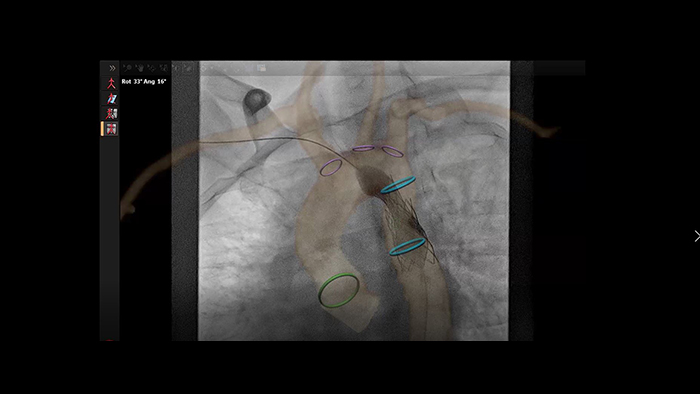

Orientação do stent de coartação aórtica com VesselNavigator